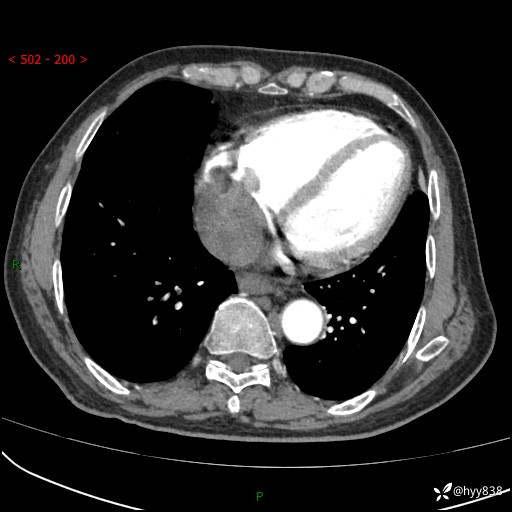

老年男性,检查发现心脏肿物1周余。少见病例,请讨论---结果公布~

主诉:检查发现心脏肿物1周余。

现病史:患者一周余前因腹胀就诊我院消化科门诊,查心脏彩超提示右房内异常回声(粘液瘤?),无明显心慌、气喘、胸闷,无明显胸痛、咳嗽咳痰等不适,活动量增加后出现心慌、气喘不适。现为求进一步治疗,就诊我科,门诊遂以“心脏肿物”收入院。 自发病以来,精神睡眠一般,食欲尚可,大小便正常,体力下降,体重无明显变化。

胸部CT平扫+增强